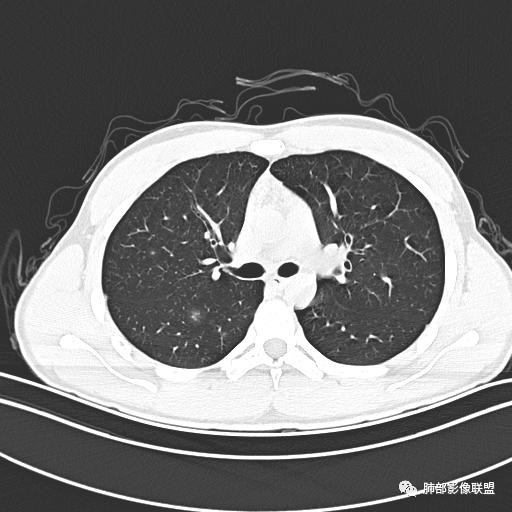

小强:青年,发热,皮疹;双肺散在结节,周围磨玻璃,点晕征,疱疹病毒感染,鉴别荚膜组织胞浆菌,结核。 大雄:青年,急性起病,发热伴全身皮疹2天,抗病毒治疗体温有下降。双肺随机分布大小不等类圆结节,“点晕征”。考虑水痘-疱疹病毒(VZV)血播询问接触史,查体皮疹分布以及形态基本可诊断。 王开金江津中心医院呼吸科:青年男性,起病急,病程短,以发热,皮疹为首发症状,感染指标以单核细胞升高为主,胸部ct双肺多发结界,周围有晕,点晕表现,随机分布,同意於老师意见,水痘疱疹病毒血流感染累及肺。 王秀仙:双肺多发大小不等结节,周围有晕,边缘模糊,呈点晕征表现。青年,急性起病,发热伴全身皮疹2天,抗病毒治疗体温有下降。考虑疱疹病毒。鉴别荚膜组织胞浆菌。 傅昌瑜:19岁男性,发热、全身皮疹2天,单核细胞增高,双肺多发结节,结节边缘见边界不清磨玻璃影。点晕征+发热、全身皮疹+单核细胞增高——考虑水痘-带状疱疹病毒肺炎。 一切∮随缘:年轻男性,发热,皮疹两天,实验室,CRP,PCT增高,影像:双肺多发散在磨玻璃结节,边界欠清,大小不等,呈点晕征改变,以血管束周围分布为主,局部血管束略增粗,其它无明显改变,考虑:1:病毒性肺炎(水痘疱疹病毒?不知道皮肤有无改变)2:真菌(组织胞浆菌,血管侵袭性肺曲霉)3:GPA4:寄生虫(实验室没有看到嗜酸细胞增高) 赵山河:双肺散在结节,周围有晕,边缘模糊,呈点晕征表现。青年,急性起病,发热伴全身皮疹2天,抗病毒治疗体温有下降。考虑水痘—疱疹病毒感染。洪桥爱:青年男性,发热、皮疹2天,伴瘙痒,皮疹于面部首发,之后进展至全身,虽然没有对皮疹进行描述,但是从出疹时间及皮疹进展情况,伴瘙痒,应该就是个水痘患者;CT提示双肺随机分布结节影,部分结节伴有边界不清晕征,考虑水痘血播肺。 刘强:年轻男性,急性起病,皮疹,发热,抗感染治疗体温下降,说明有效。影像表现为散在点晕征,感染类疾病谱(疱疹病毒,真菌,结核),结合年龄,皮肤皮疹,考虑水痘-疱疹病毒性肺炎。 小兜:男性,19岁,发热皮疹两天,颜面部至全身,CRP,降钙素及单核增高。CT示双肺散在小结节,周围伴磨玻璃影,点晕征,考虑为水痘-带状疱疹病毒(varicella-zoster virus,VZV)肺炎 必有路:青年,皮疹+发热+“点晕征”→水痘-疱疹病毒(VZV) 许慧良:青年男性患者,发热、皮疹2天,体温最高38.5℃,第3天皮疹扩展至全身,伴瘙痒,胸部CT:双肺多发随机分布的小结节,结节周边见边界模糊的晕征,考虑水痘病毒感染流心明智:男,19,急性起病,发热伴全身皮疹2天。出疹顺序头→全身,抗病毒有效。胸部CT:两肺多发大小不等类圆形实性小结节影,随机分布,结节周围环绕GGO,边界模糊,呈点晕征。出疹特点是关键,未提示。考虑:血播病毒性肺炎,水痘-疱疹病毒?麻疹?鉴别荚膜组织胞浆菌、TB、血管炎、寄生虫等。 浪迹天涯:病灶多为5-10mm大小结节,结节周围可见磨玻璃样的晕环,常多发,可分布于肺内任何区域,考虑水痘—带状疱疹病肺炎如果短时间内有新的一个区域浸润,更加能说明,